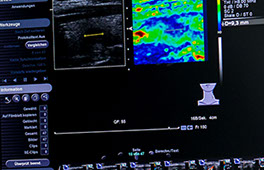

Die Elastografie ist eine besondere Ultraschalluntersuchung, in der die Festigkeit oder Elastizität eines Organes, oder einer Struktur in einem Organ, gemessen wird.

Mit der Elastografie ist nun ein wertvolles zusätzliches Merkmal, die Festigkeit eines Knotens, hinzugekommen: je härter, fester, unelastischer ein Knoten ist, desto wahrscheinlicher ist es, dass er aus bösartigen Zellen besteht (dies insbesondere dann, wenn die bereits bekannten Merkmale wie Echoarmut, unregelmäßige Begrenzung, ovale Form, Mehrdurchblutung, Kalkeinlagerungen zusätzlich vorhanden sind).